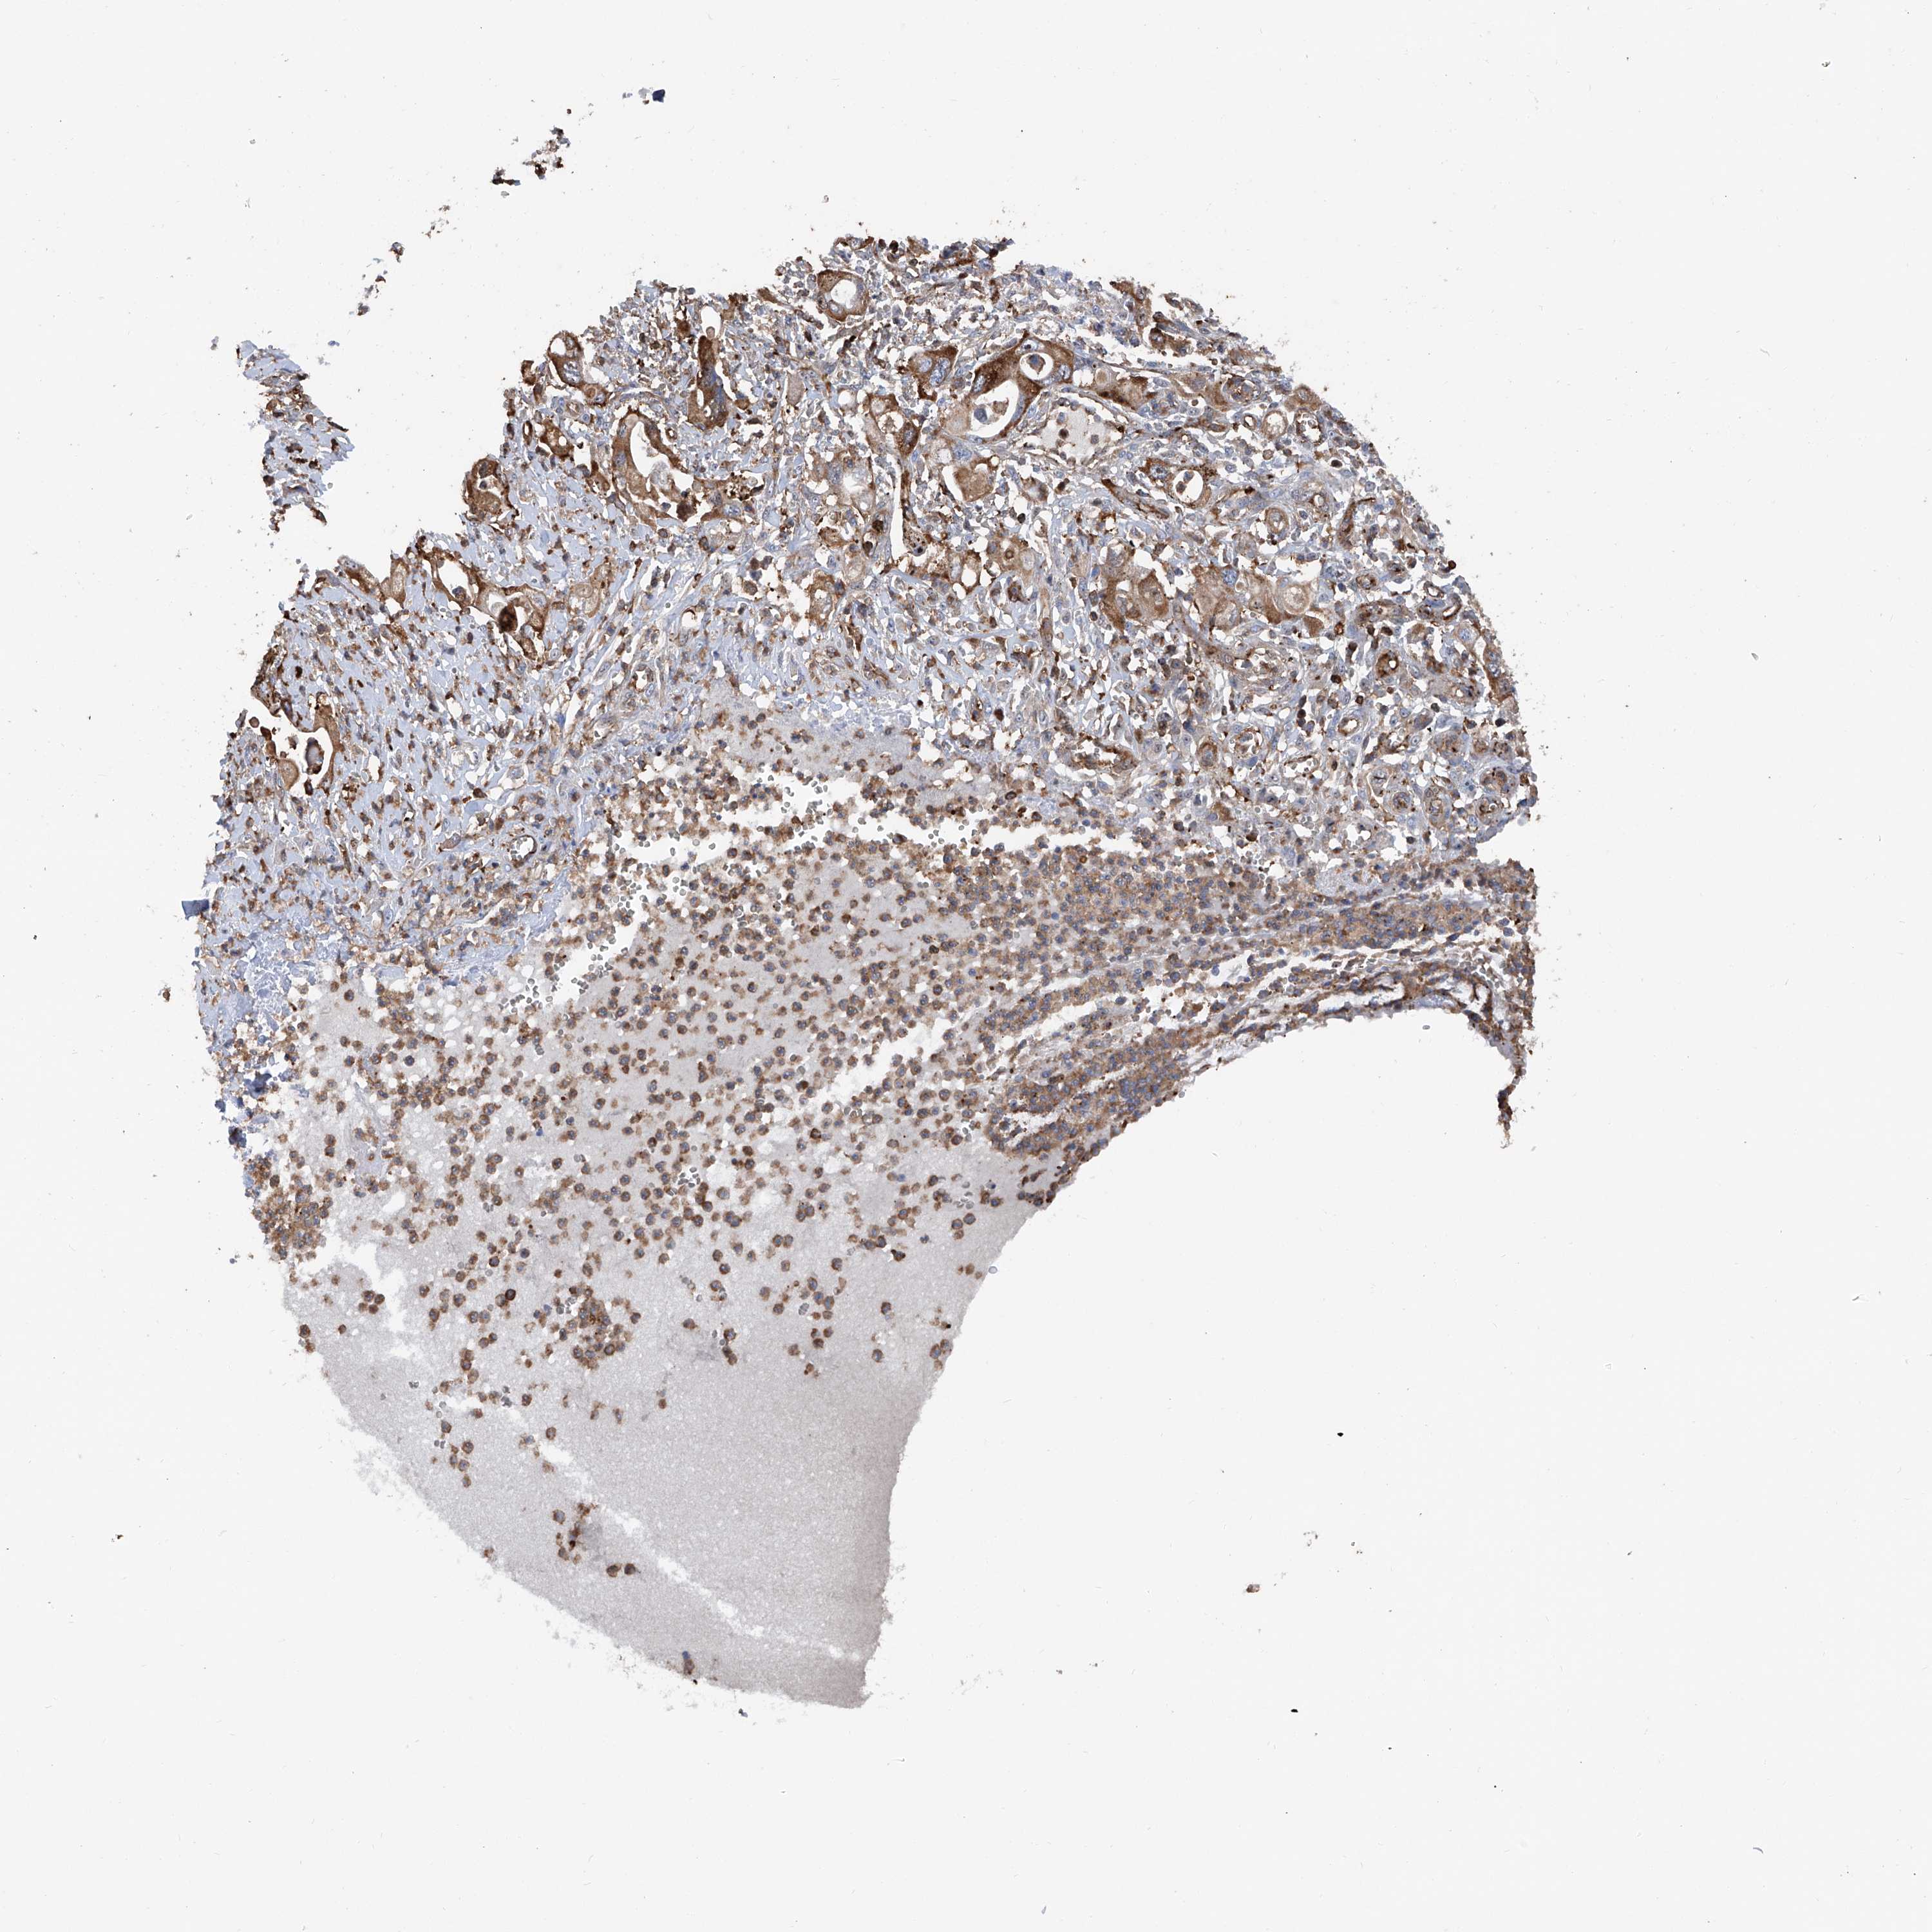

PANCREATIC CANCER - Protein expressioni

A mouse-over function shows sample information and annotation data. Click on an image to view it in a full screen mode. Samples can be filtered based on level of antibody staining by selecting one or several of the following categories: high, medium, low and not detected. The assay and annotation is described here.

Note that samples used for immunohistochemistry by the Human Protein Atlas do not correspond to samples in the TCGA dataset.

Antibody stainingi

Antibody staining in the annotated cell types in the current human tissue is reported as not detected, low, medium, or high, based on conventional immunohistochemistry profiling in selected tissues. This score is based on the combination of the staining intensity and fraction of stained cells.

Each image is clickable and will lead to virtual microscopy that enables deeper exploration of all samples and also displays staining intensity scores, fraction scores and subcellular localization as well as patient and tissue information for each sample.

Antibody HPA028973

Staining

High

Medium

Low

Not detected

Intensity

Strong

Moderate

Weak

Negative

Quantity

>75%

75%-25%

<25%

None

Location

Nuclear

Cytoplasmic/membranous

Cytoplasmic/membranous,nuclear

Adenocarcinoma, NOS